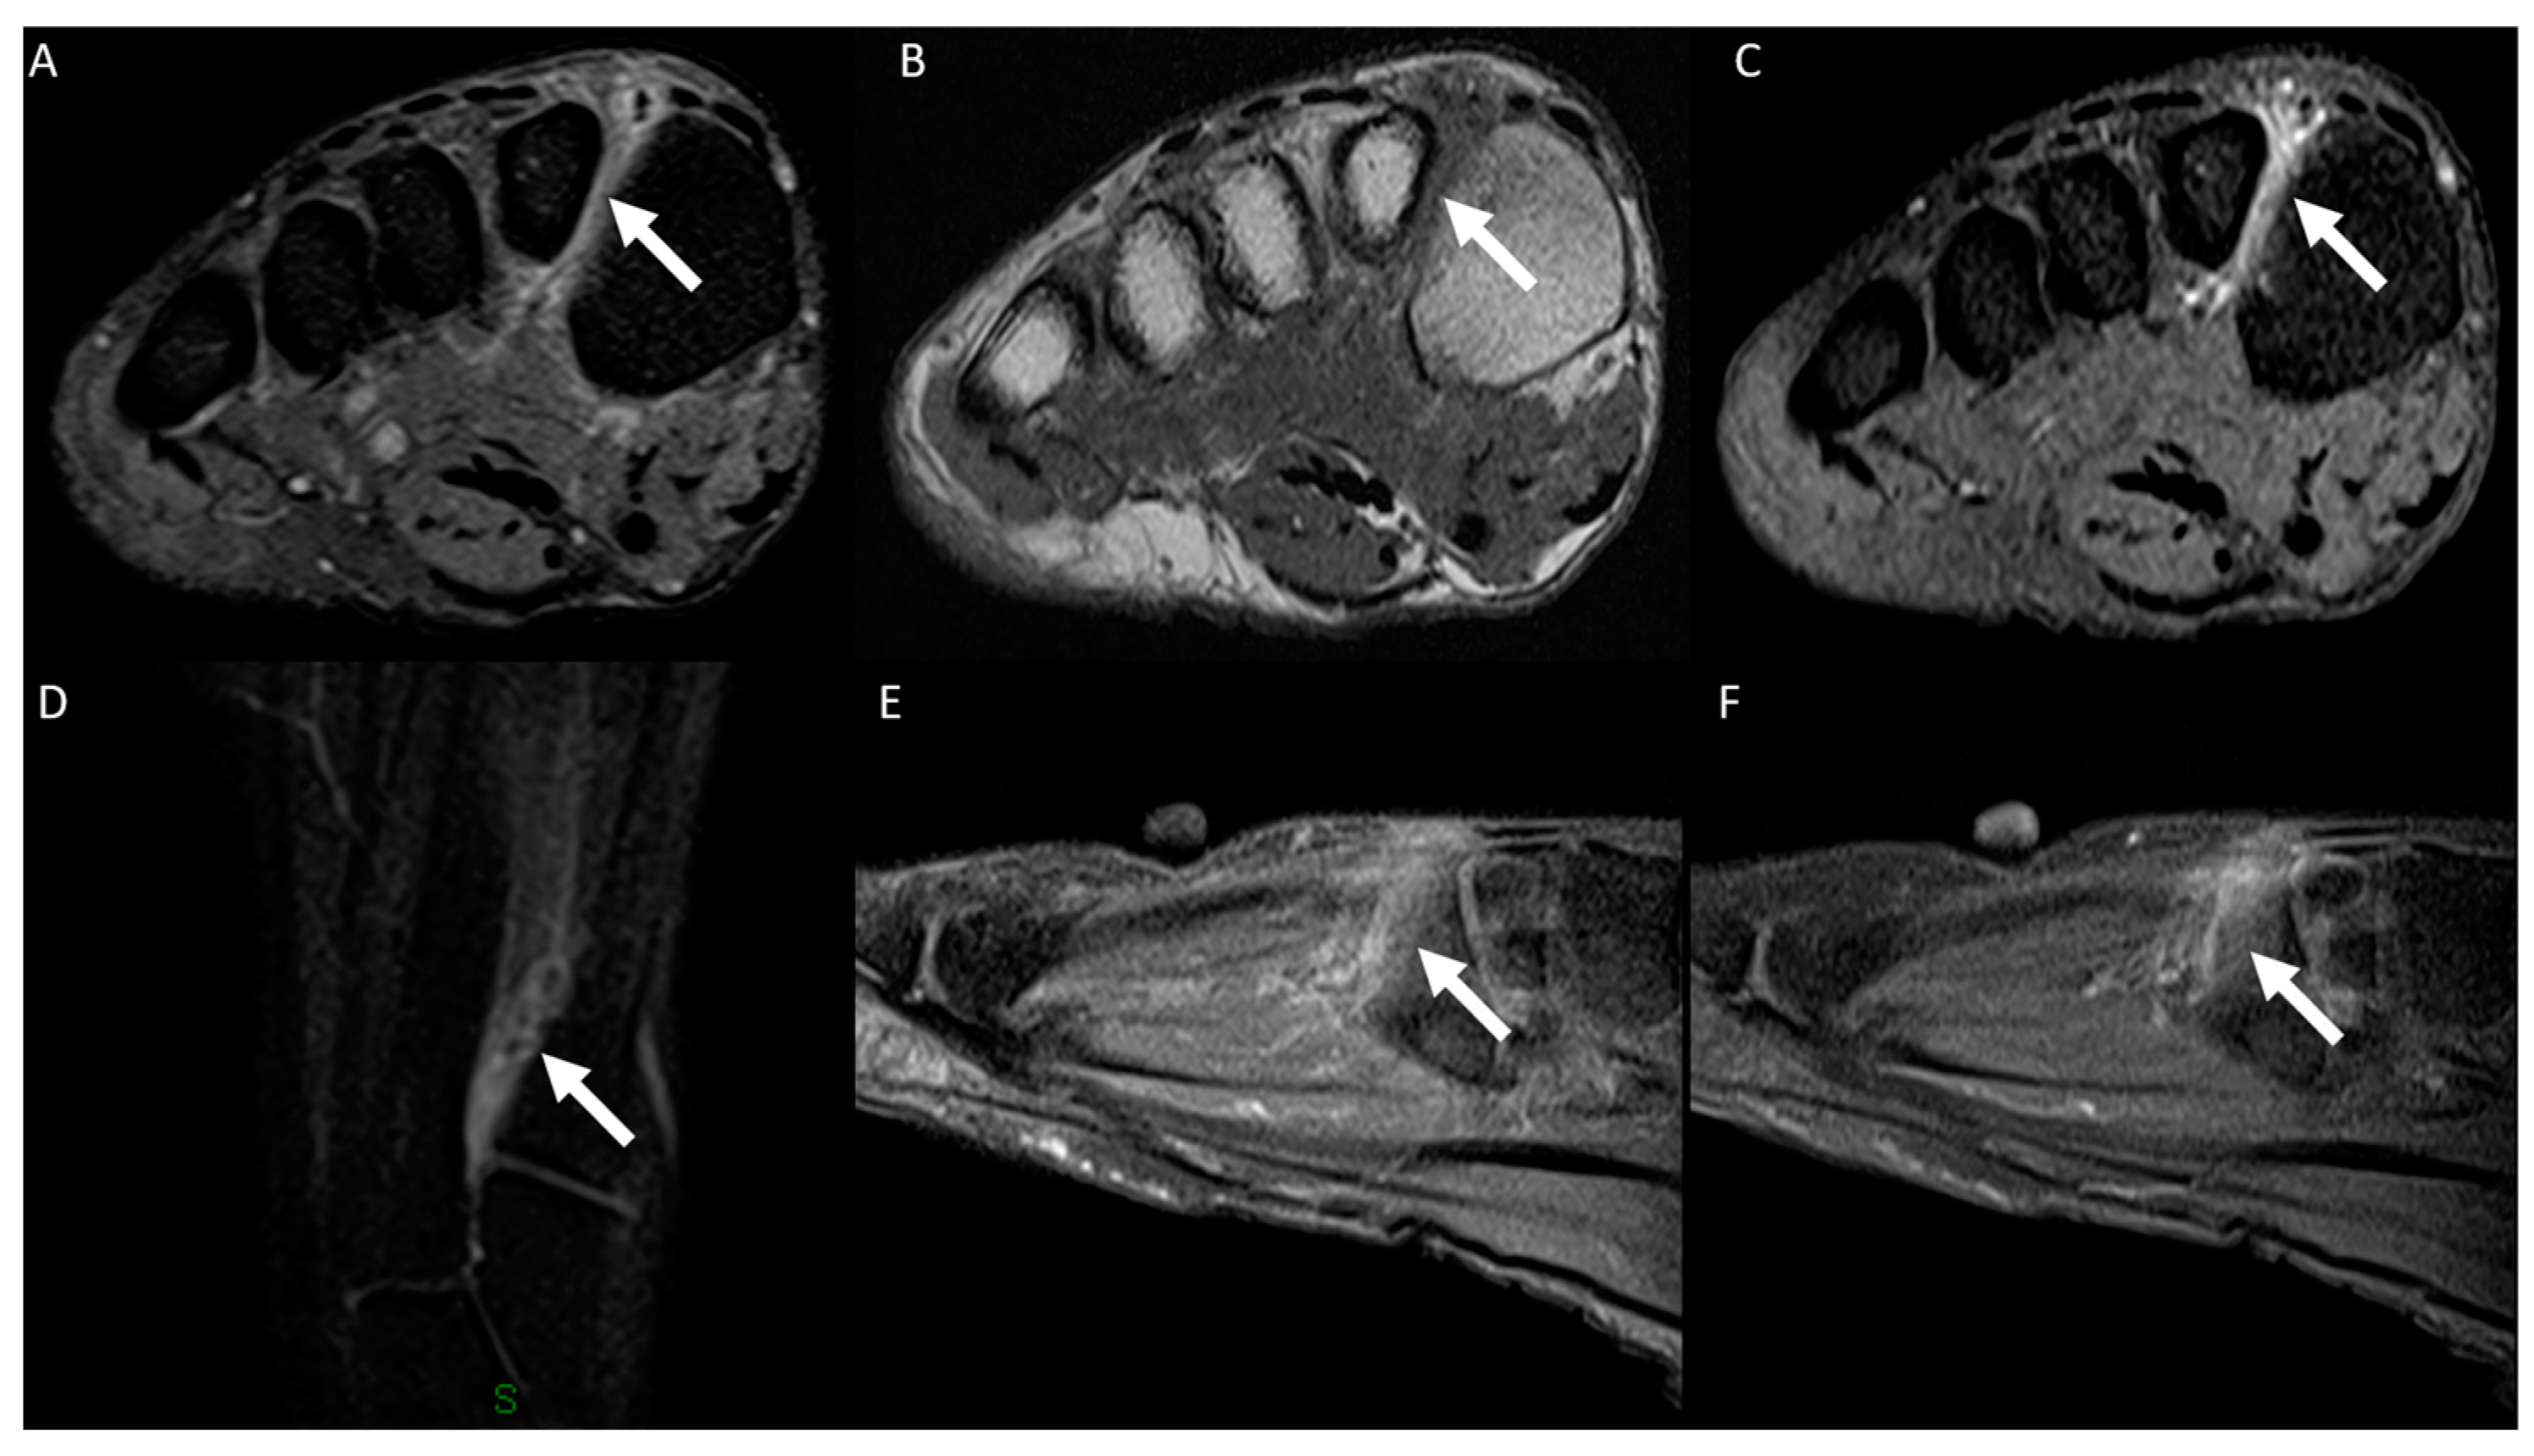

3.2. Distribution of MRI Findings